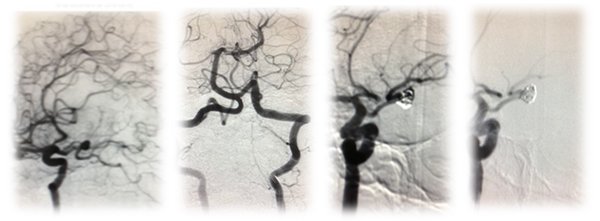

El portar un Aneurisma Cerebral es padecer una enfermedad grave; la morbi-mortalidad por rotura de un aneurisma cerebral es todavía alta. Presentamos a una paciente de 52 años de edad que sufre Ictus; evaluada clínica-radiológicamente: WFNS II Sano II Fisher III, aneurisma del sistema del complejo Posterior en su segmento P1 (2.5x 7 mm) por AngioTEM; se evaluó los dos sistemas arteriales y se optó por el mejor acceso, procedimos a la embolización con coil de desprendimiento, con buen resultado clínico y angiográfico.

Los resultados fueron tomados en cuenta basándose en la evaluación de los dos sistemas arteriales y se optó por el mejor acceso del tratamiento Endovascular; procediendo a la embolización del aneurisma a nivel de P1 por la arteria carótida interna mediante la comunicante posterior con persistencia embrionaria carótida-basilar (presencia de una arteria comunicante posterior prominente) mediante coil de desprendimiento, con buen resultado clínico y angiográfico con exclusión adecuada del aneurisma